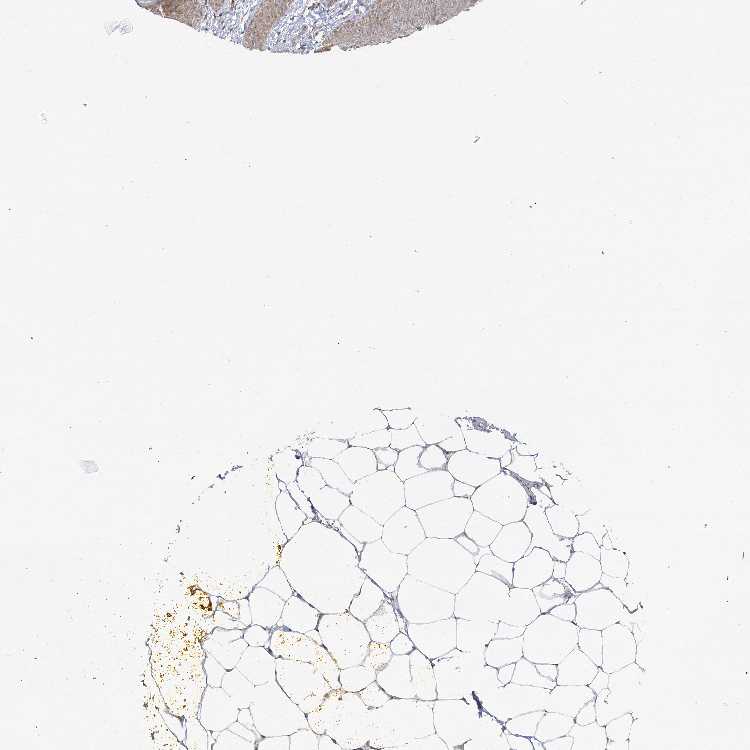

ADIPOSE TISSUE - Antibody stainingi

Antibody staining in the annotated cell types in the current human tissue is reported as not detected, low, medium, or high, based on conventional immunohistochemistry profiling in selected tissues. This score is based on the combination of the staining intensity and fraction of stained cells.

Each image is clickable and will lead to virtual microscopy that enables deeper exploration of all samples and also displays staining intensity scores, fraction scores and subcellular localization as well as patient and tissue information for each sample.

Antibody HPA037980

Adipocytes Medium

ADIPOSE TISSUE - HPA RNA-seqi

The RNA-seq details section shows detailed information about the individual samples used for the transcript profiling and results of the RNA-seq analysis.

Information about each individual sample is listed below, including gender, age, a tissue section image and estimated fractions of cell types. nTPM (normalized transcripts per million) values give a quantification of the gene abundance which is comparable between different genes and samples.